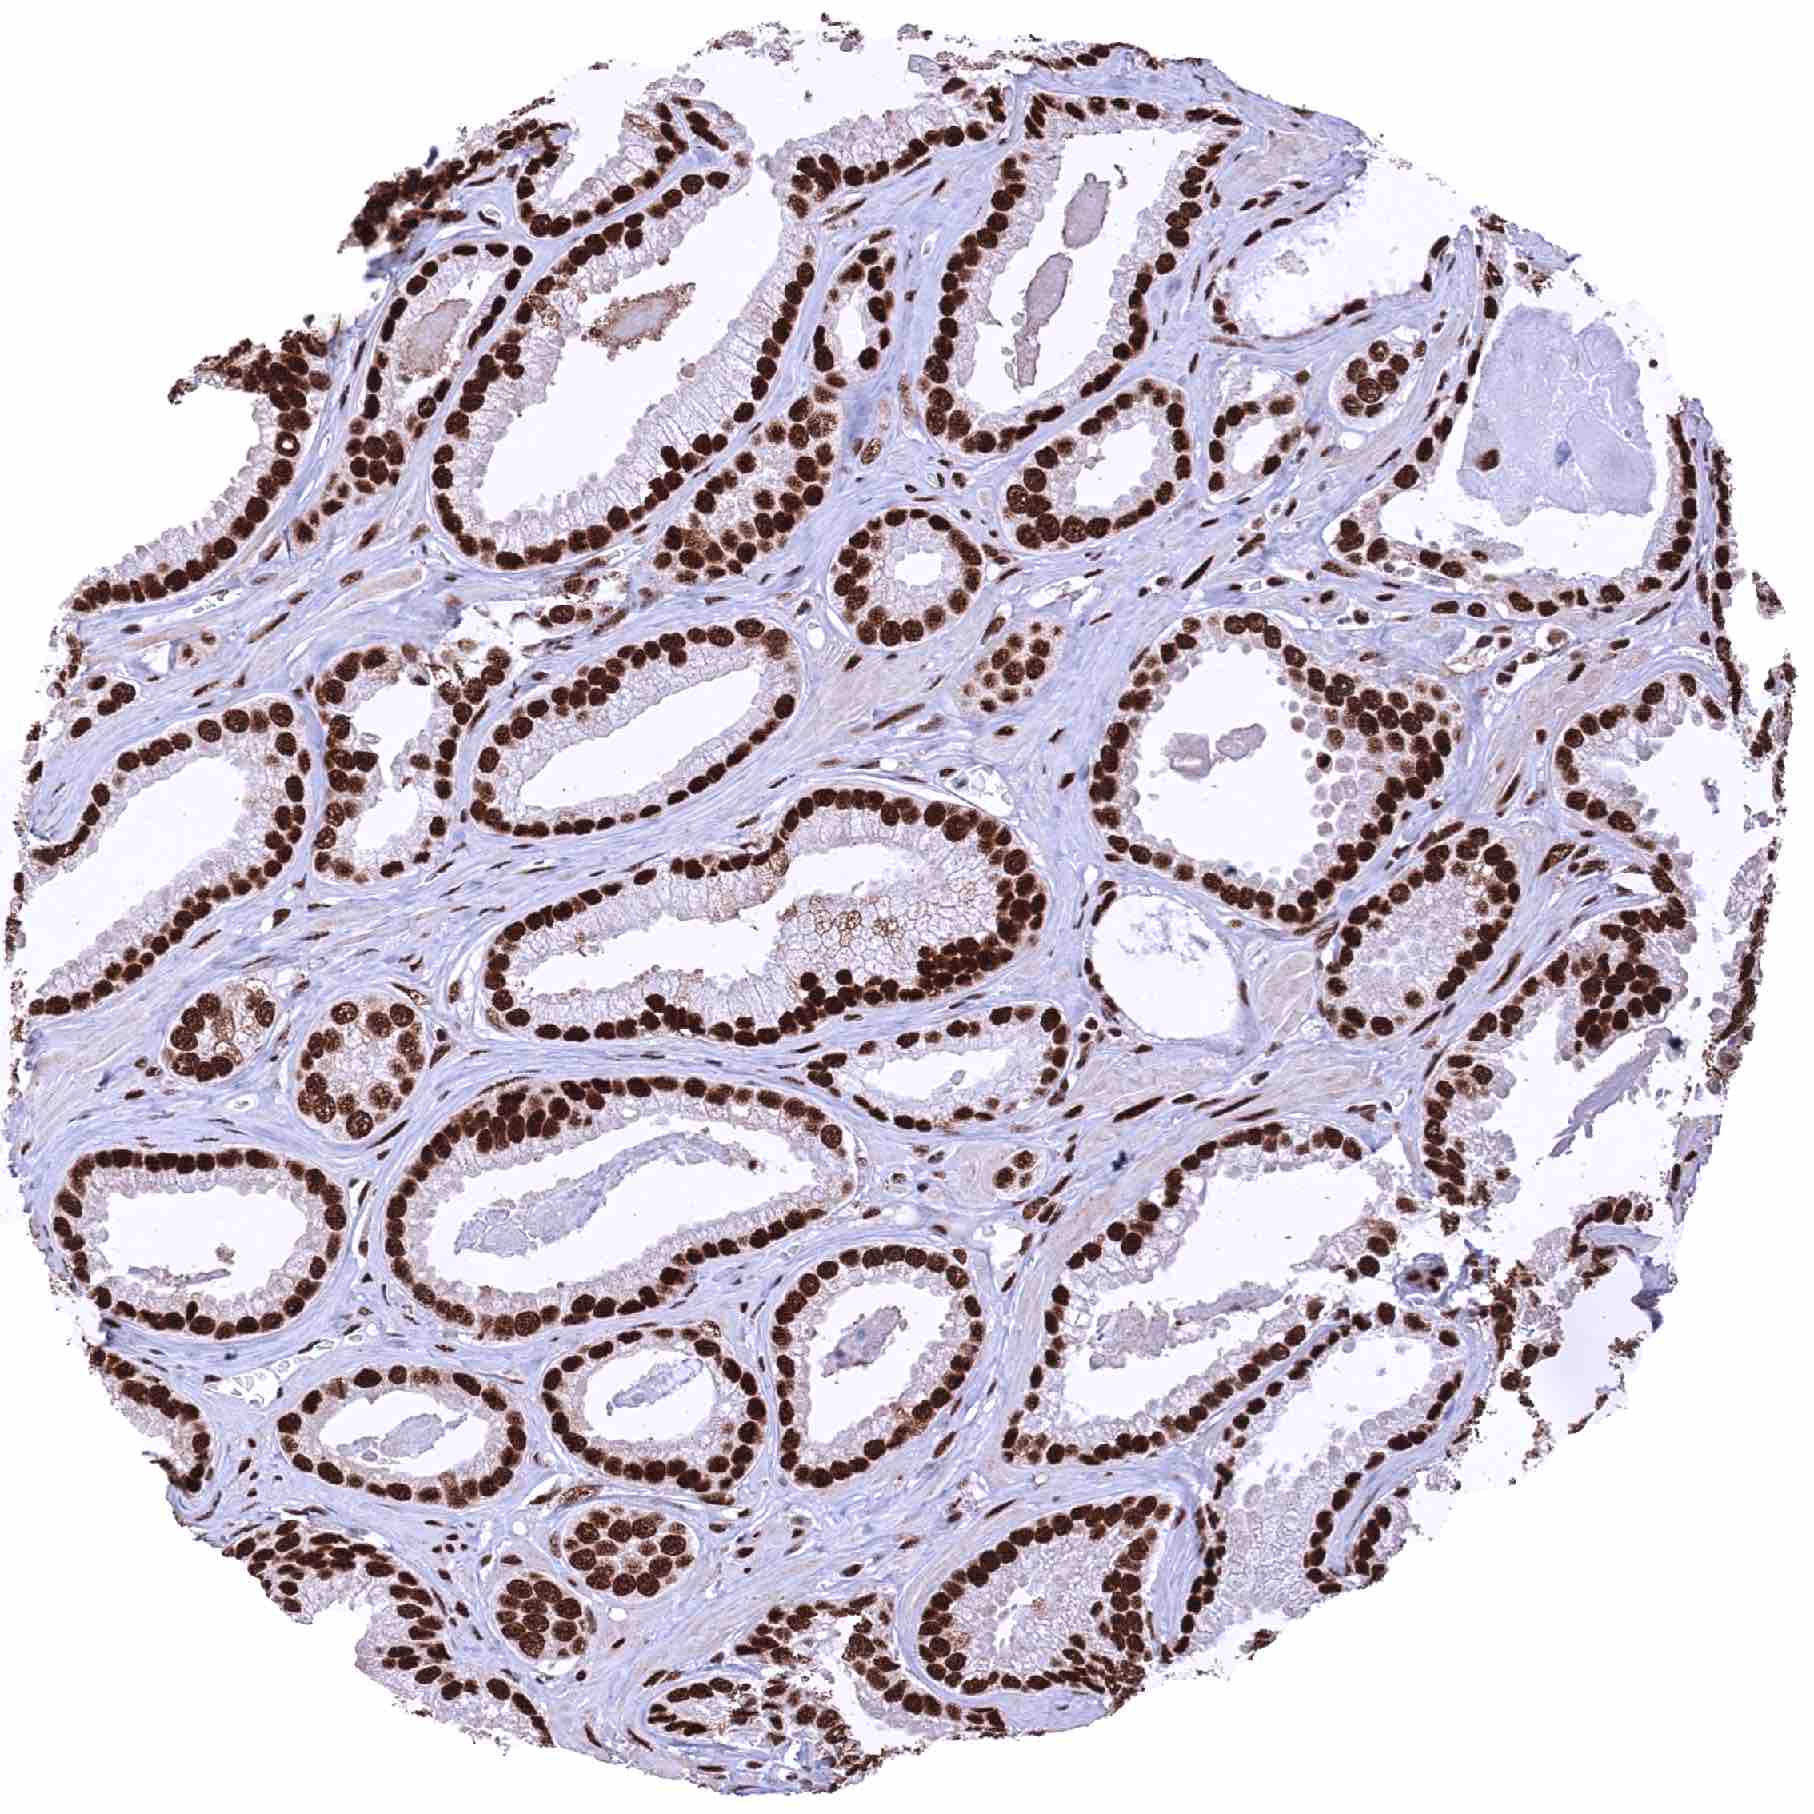

Prostate – Adenocarcinoma (Gleason 3+3=6) showing an intense nuclear MRE11 immunostaining of tumor cells